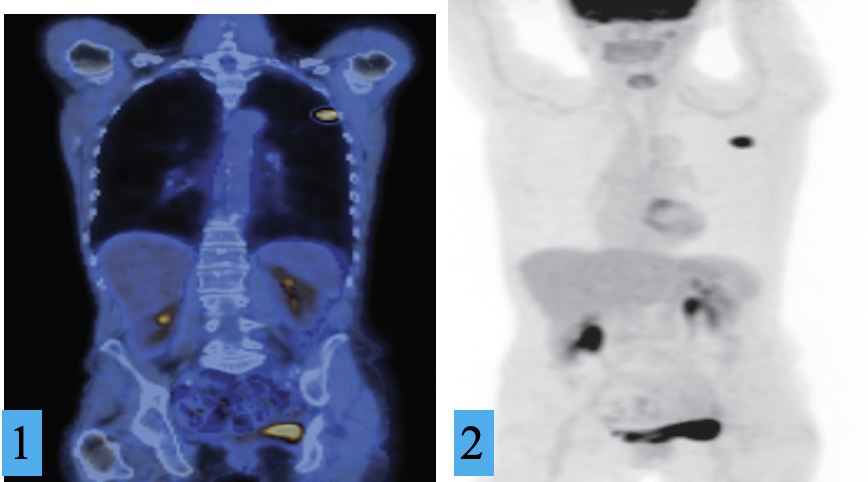

FDG-PET/CT of lung cancer. Z

1) Coronal CT image and

2) maximum intensity projection, demonstrating a small left lung cancer.

The remainder of the FDG uptake is physiological